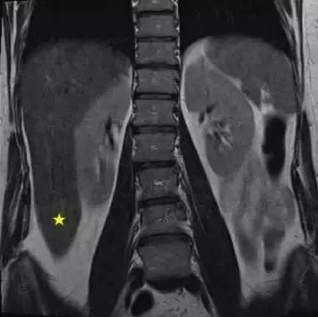

冠状面,它是人体分为前、后两部分的切面。下图是腰椎的一个MRI的冠状面图。